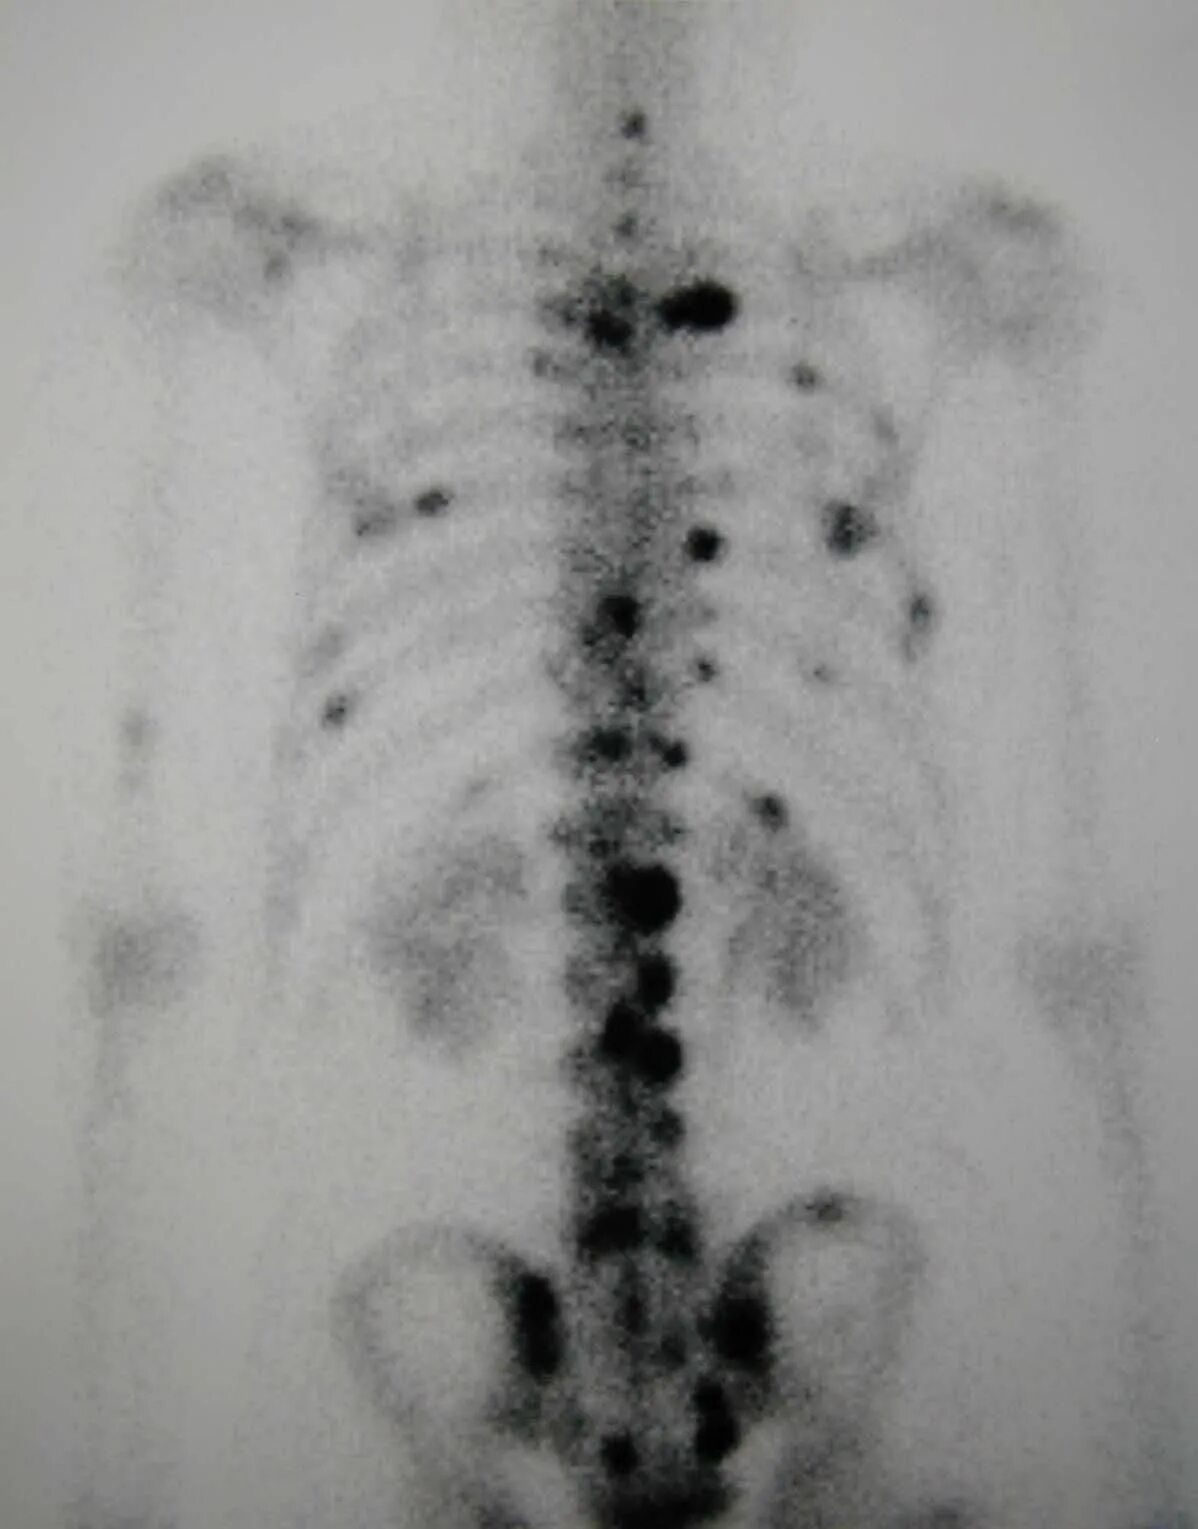

Метастазы скелета